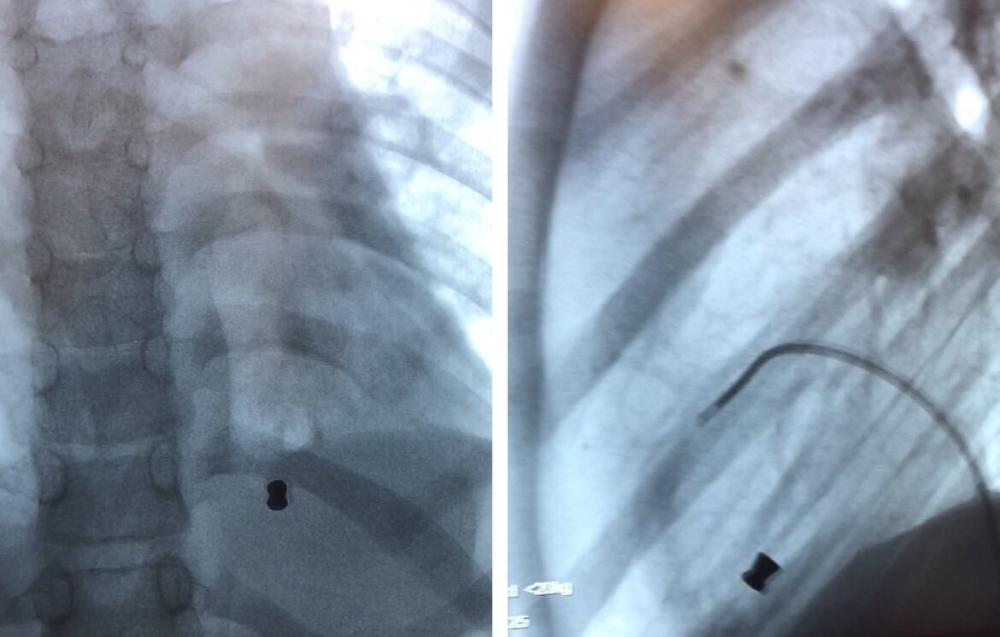

تمكن فريق القسطرة الطبي في وحدة أمراض وجراحة قلب الأطفال بمركز الأمير سلطان لطب وجراحة القلب بالقصيم من استخراج رصاصة من قلب طفل عن طريق القسطرة من دون الحاجة إلى عملية جراحية بنجاح تام.

وذكر الدكتور عبدالله القويعي استشاري أمراض القلب والقسطرة أن مركز القلب استقبل طفلاً يبلغ من العمر 11 عاماً بعد إصابته برصاصة بندقية هوائية أثناء عبثه بها، حيث اخترقت القفص الصدري واستقرت في الجهة اليمنى من القلب، مضيفاً أن حالة الطفل من الحالات النادرة الحدوث، حيث تم على الفور تنويمه في العناية المركزة القلبية والتأكد من استقرار حالته الصحية ثم تحويله لمعمل القسطرة، وبفضل من الله تم استخراجها من القلب في وقت قياسي دون أي مضاعفات أو حاجة للجراحة، وقد خرج الطفل من المستشفى ولله الحمد.